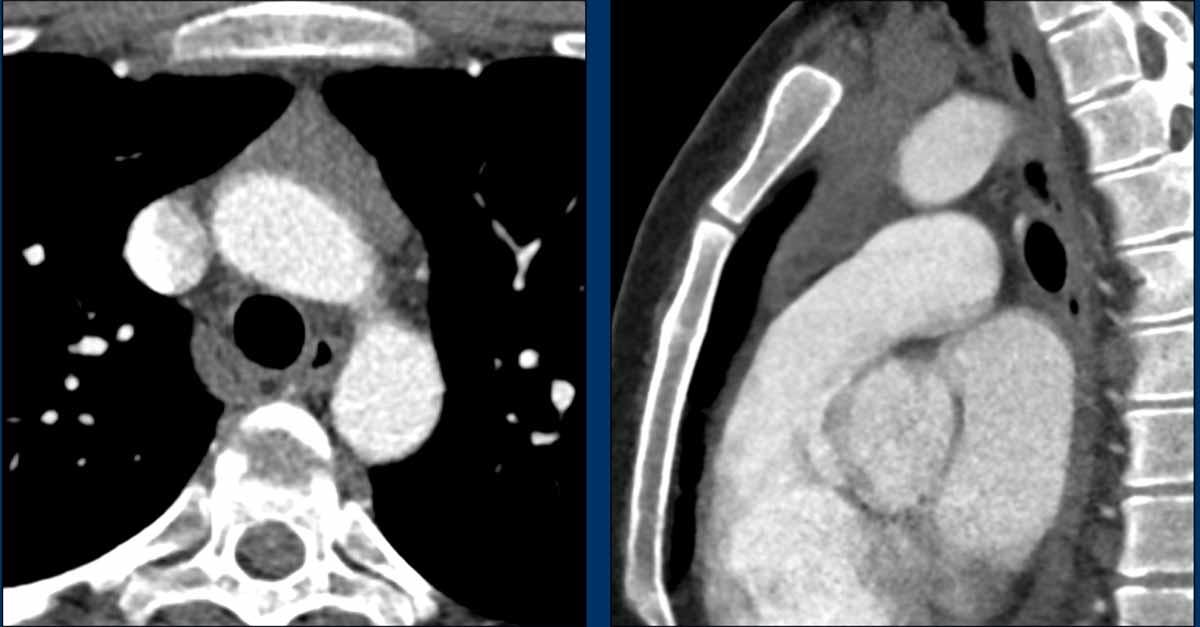

Các hình ảnh này của một phụ nữ 65 tuổi có tiền sử mắc bệnh Graves, một rối loạn tự miễn liên quan đến tình trạng cường chức năng tuyến giáp.

CT được thực hiện vì lý do ho ra máu.

Hình ảnh

Có một tuyến ức to lớn, cồng kềnh chứa mô mỡ đại thể.

Đây là hình ảnh điển hình của tăng sản tuyến ức.

Tăng sản tuyến ức trong bệnh Graves có liên quan đến tình trạng dư thừa hormone tuyến giáp và kháng thể kháng thụ thể thyrotropin.

Tình trạng này thường cải thiện sau khi điều trị thành công bệnh Graves.

Mặc dù không thực sự cần thiết, MRI vẫn được thực hiện.

Hình ảnh chuỗi xung gradient-echo nhanh pha đối (out-of-phase) cho thấy sự mất tín hiệu như dự kiến.

CT cho thấy tuyến ức trở về bình thường sau khi điều trị bệnh Graves.

Khi đo cường độ tín hiệu, bạn sẽ nhận thấy sự sụt giảm cường độ tín hiệu.

Tỷ lệ phần trăm sụt giảm tín hiệu này được gọi là chỉ số cường độ tín hiệu (SII).

Chỉ số cường độ tín hiệu

Chỉ số cường độ tín hiệu (SII) là lượng tín hiệu bị mất đi chia cho lượng tín hiệu ban đầu.

SII lớn hơn 9% có độ nhạy và độ đặc hiệu 100% trong chẩn đoán tăng sản tuyến ức.

SII đáng tin cậy hơn so với tỷ số dịch chuyển hóa học.

Trong trường hợp này, SII là 77%.